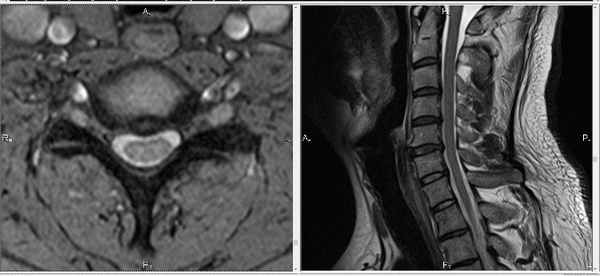

МРТ шейного отдела позвоночника: норма

МРТ поясничного отдела позвоночника: 1. норма 2. метастазы

МРТ грудного отдела позвоночника: 1. норма 2. опухоль

Шея вмещает в себя много органов. На МРТ шеи видны позвоночник, горло, гортань, трахея, щитовидная и паращитовидная железа, кровеносные сосуды и др. Шея – это анатомическое наиболее подвижна часть тела. Поэтому наиболее частым объектом исследования при МРТ шеи является шейный отдел позвоночника. МРТ исследование показывает состояние не только шейных позвонков, но и дисков. Как правило проводится измерение сечения позвоночного канала на уровне выпячивания дисков, что есть крайне важной информацией для принятия решения о лечении. Следует отметить, что эти показатели важны при МРТ исследовании любого отдела позвоночника.

Небольшого размера грыжа шейного отдела позвоночника:

Такого размера грыжи могут протекать бессимптомно.

На МРТ снимке, который ниже, видны не только нижнешейный отдел позвоночника, но и грудной. Удачное сочетание, поскольку шейно-грудной переход нередко бывает причиной боли:

При длительных и упорных болевых проявлениях со стороны позвоночника, кроме МРТ шеи иногда приходится делать и МРТ исследование грудного отдела. Это нужно для дифференциальной диагностики. Пример — метастатическое поражение грудного отдела могут давать боли и в шее: